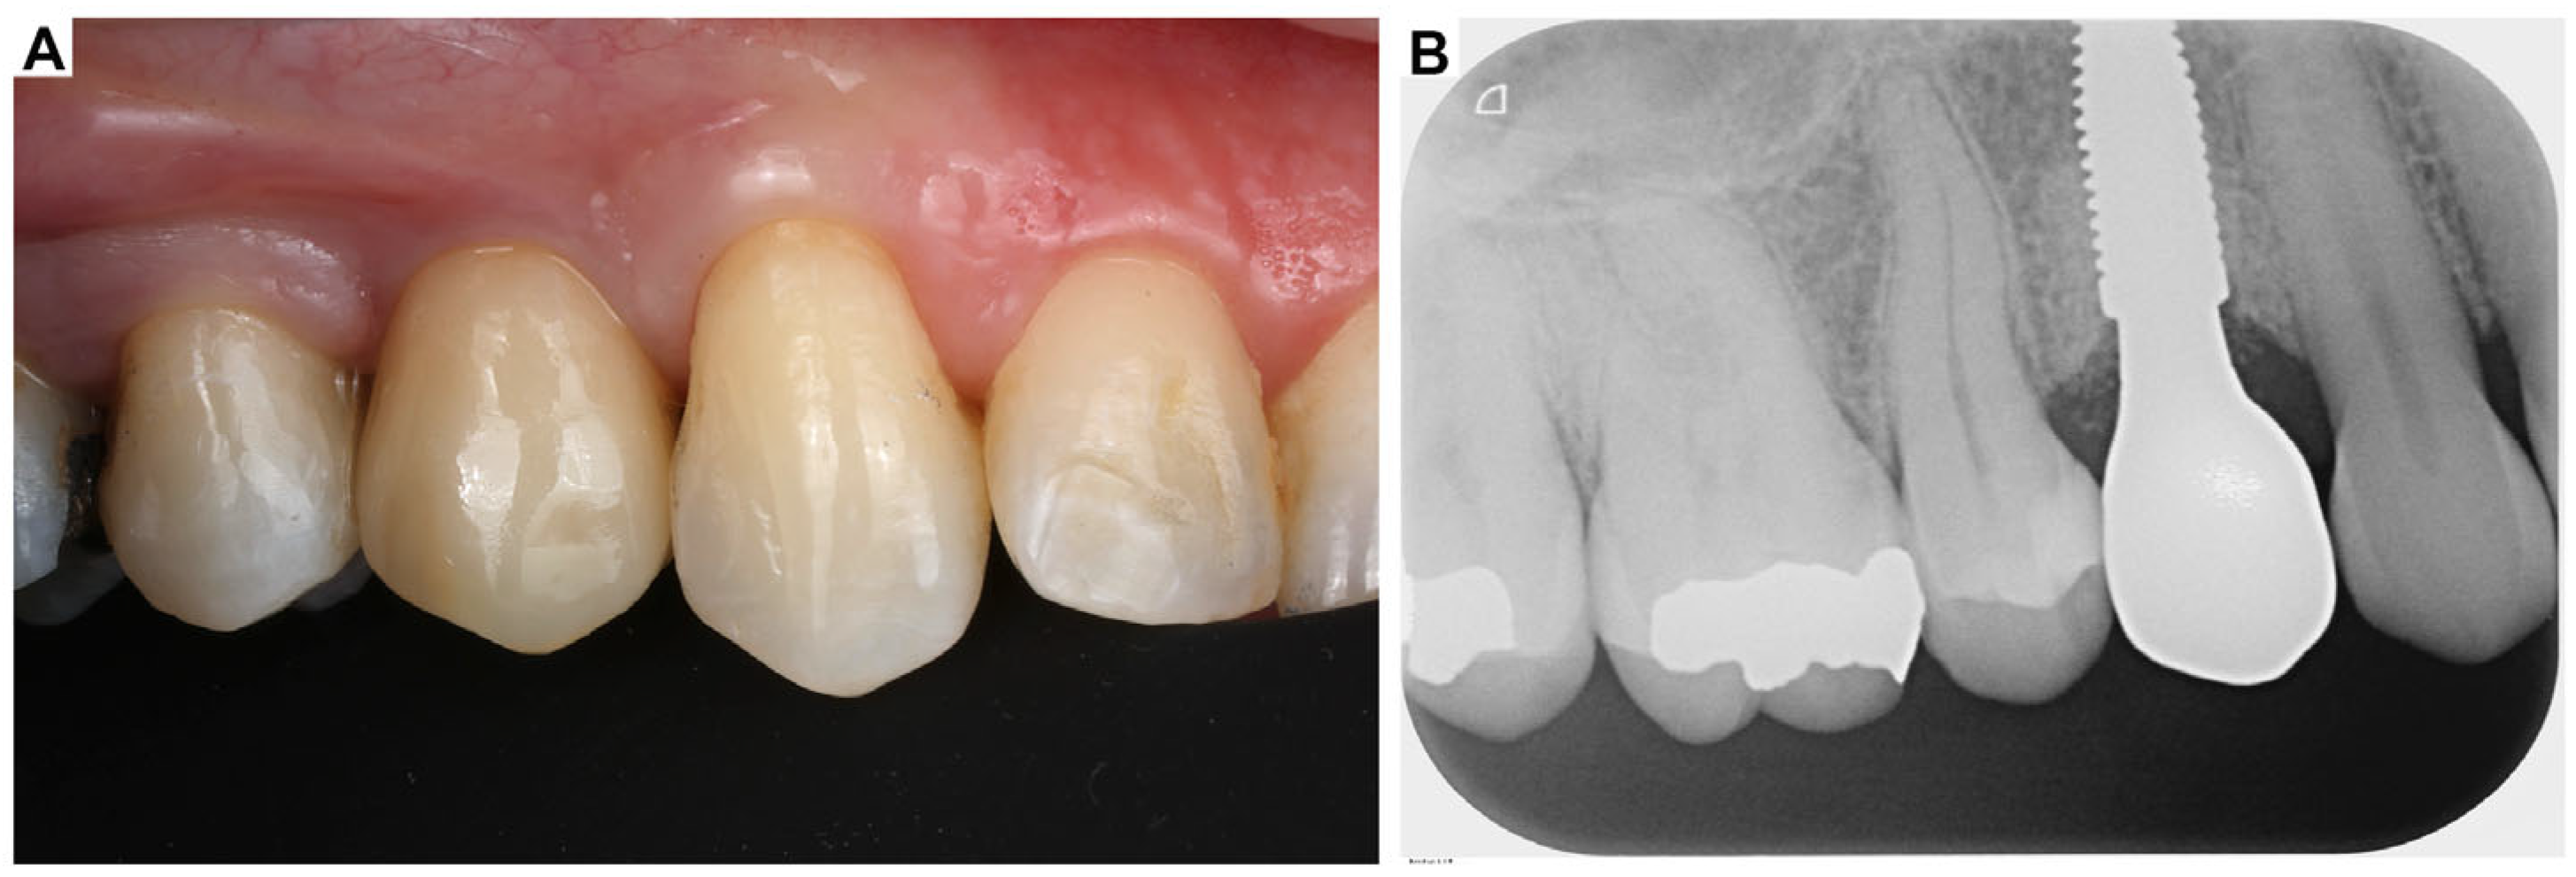

3. Clinical Cases Presentation of Advanced Implant Surgeries

3.1. Case Report-1

3.2. Case Report-2